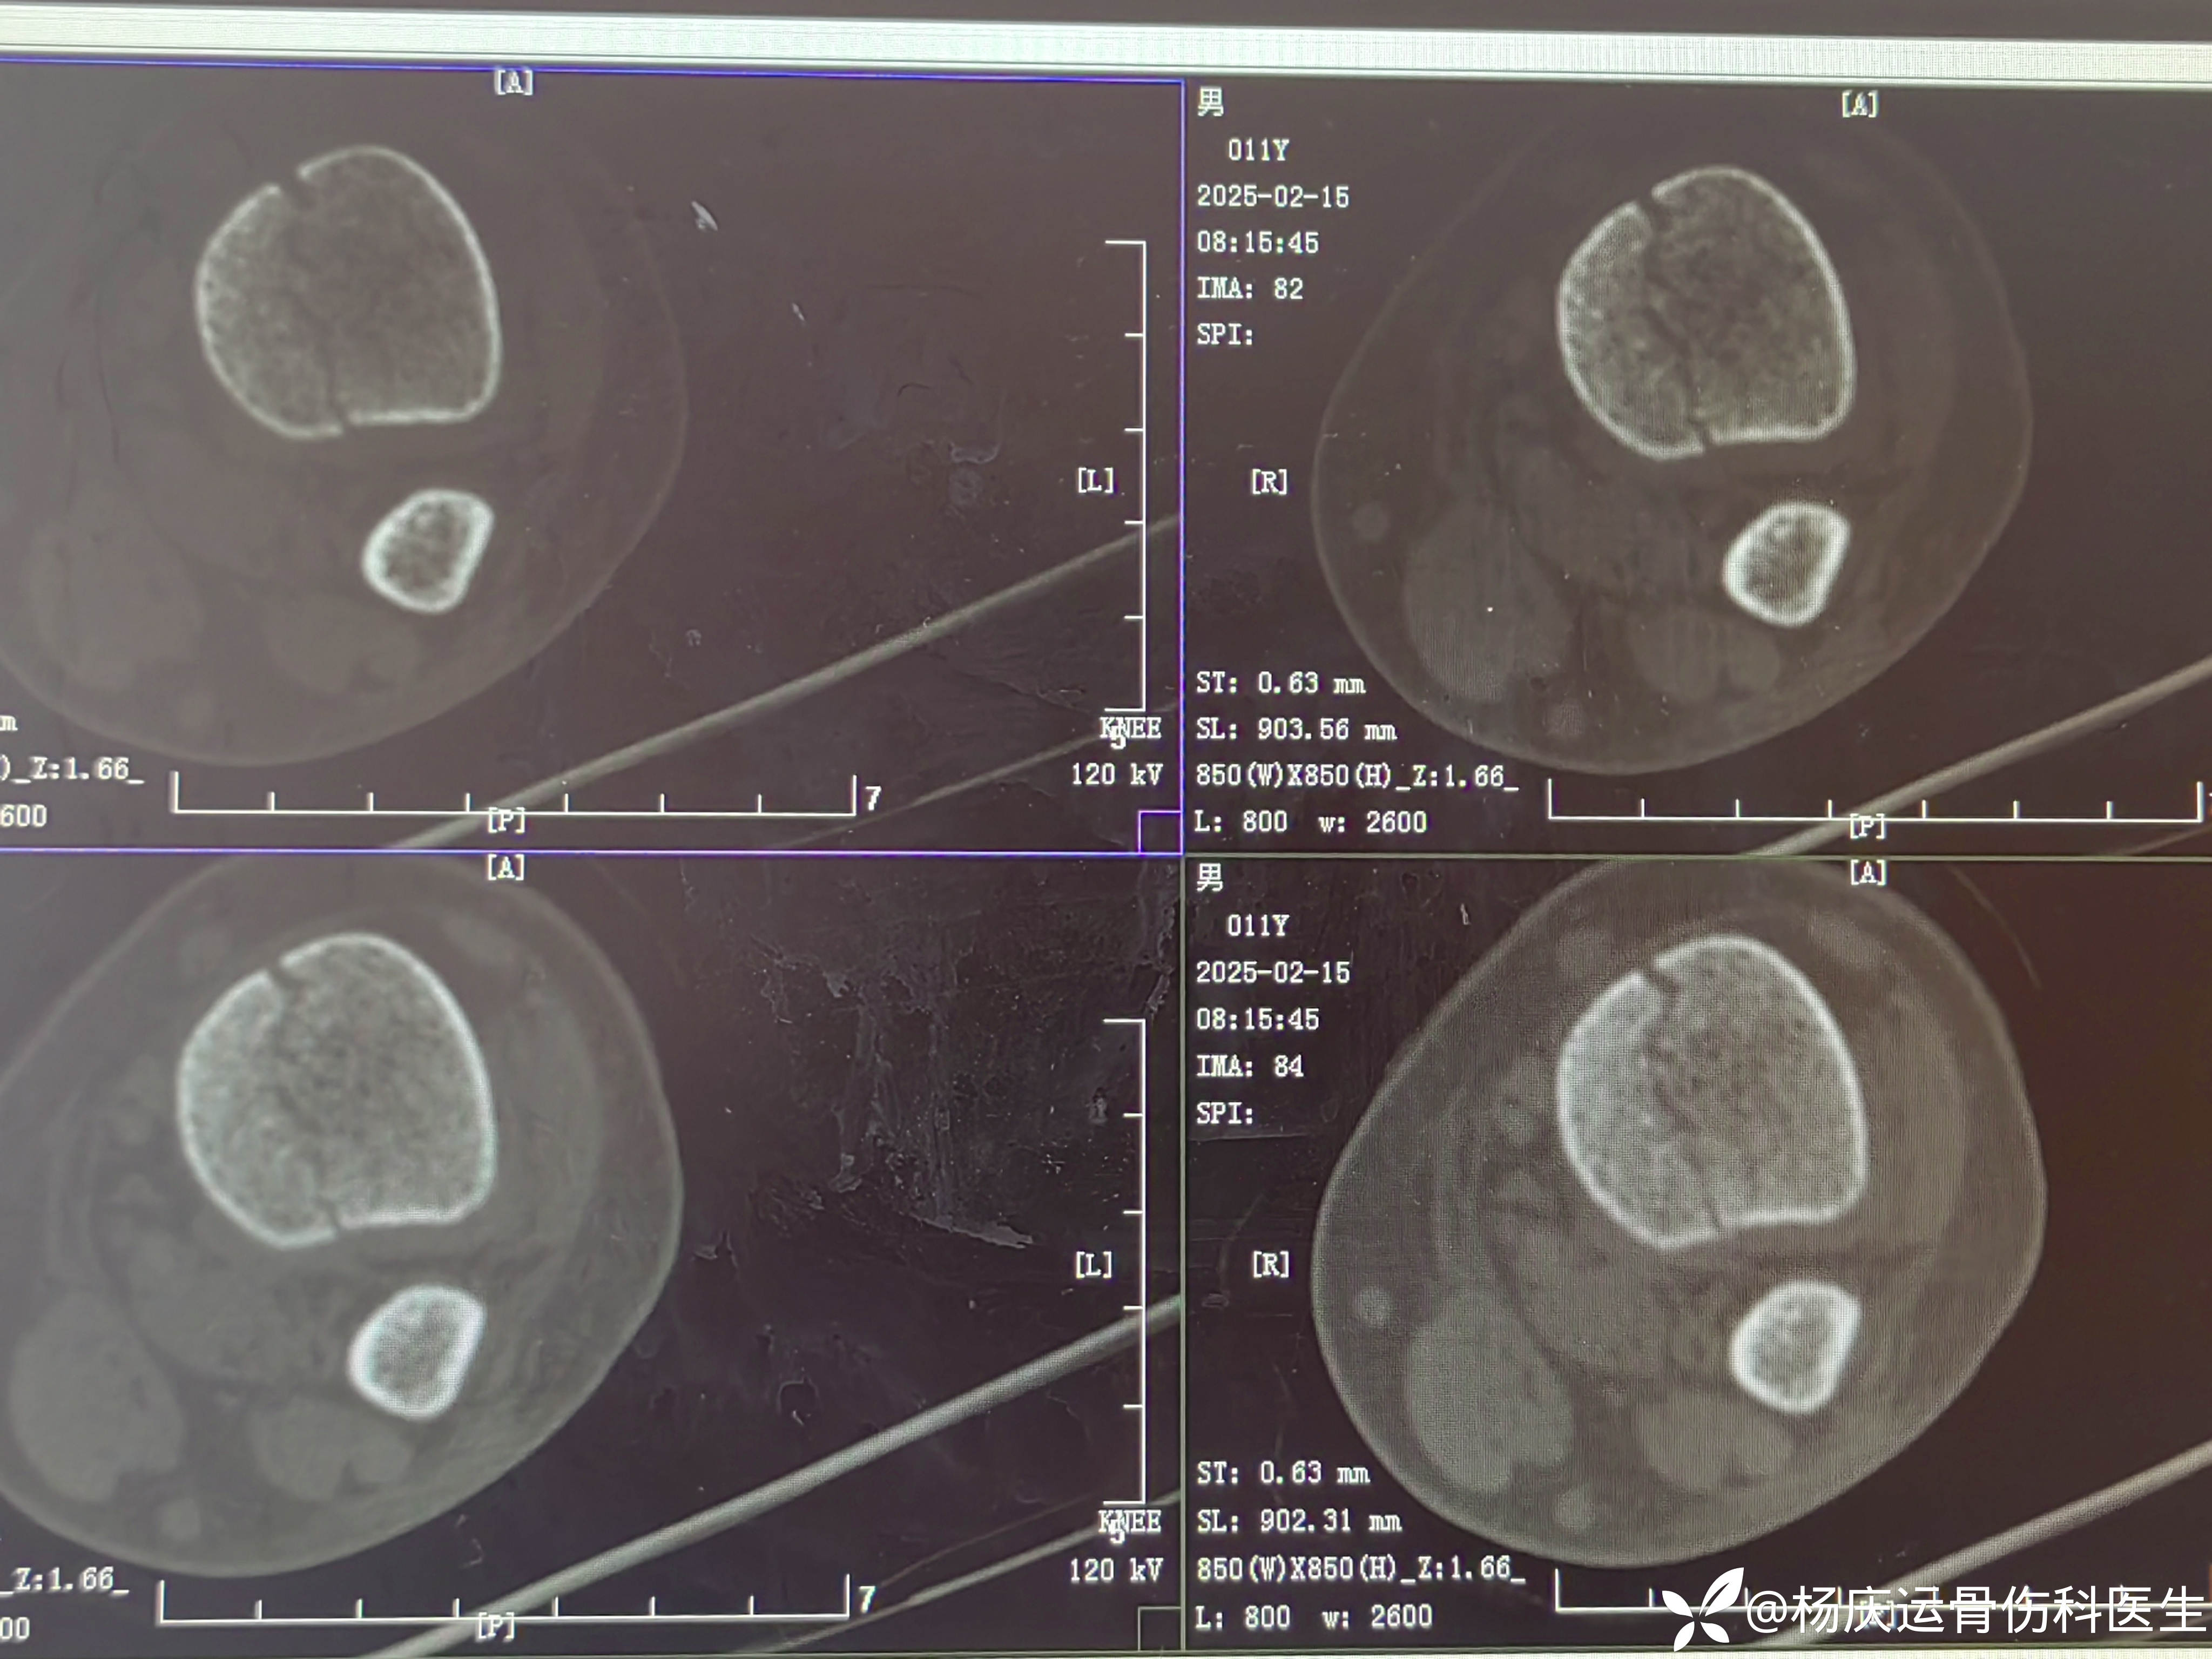

首诊CT

骨折间隙3.0mm

MRI显示骨折间隙仍大

再次复位后CT,断端间隙1.0mm(符合保守治疗标准<2mm)